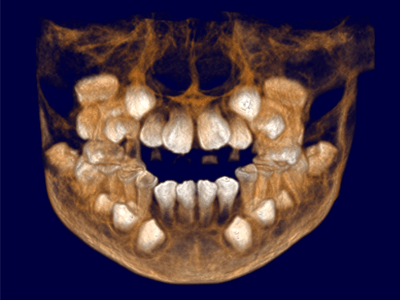

Pro Patient: Our state-of-the-art cone-beam computed tomography (CBCT) technology could selectively image the sinus, oral maxillofacial, para-nasal sinuses, ear & throat regions.

3D Imaging with Field of View sizes available in:

Proactive Dental Management thru our 3D Imaging Manipulation Software

With Oral Maxillofacial CT Scans, your dentist enhances his ability to proactively manage your health concern thru accurate diagnosis & better treatment planning. Moreover, the patient benefits from a painless,low radiation dose CT Scan procedure.